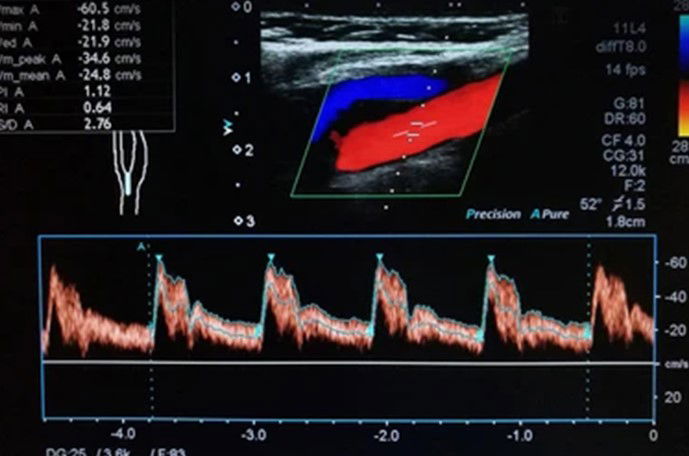

Our Colour Doppler ultrasound service utilizes state-of-the-art technology to produce detailed images of blood flow and detect any abnormalities in the vascular system. With our expertise and advanced equipment, we provide accurate diagnostic imaging for various medical conditions.